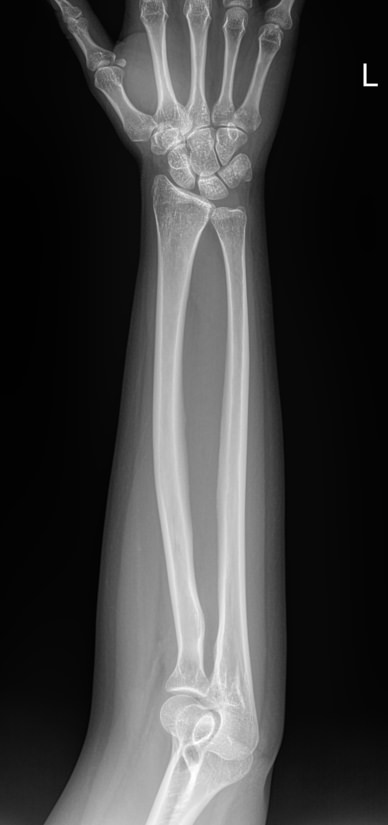

В предплечье входят 2 кости ― лучевая и локтевая. Вместе они соединяют кисть с плечом и обеспечивают движение и повороты руки. Переломы костей происходят в наиболее тонких местах ― ближе к суставам. Реже встречаются костные и мышечные патологии и онкология.

Обследование поврежденного или пораженного предплечья начинают с рентгенографии. Современное оборудование несет минимальное количество обучения и позволяет делать несколько снимков подряд, например, для контроля хирургического лечения. В снимок кроме собственно локтевой и лучевой кости попадают оба смежных сустава ― локтевой и лучезапястный. Также видны и мягкие ткани.

Что покажет рентген предплечья

• Костно-травматические изменения лучевой и локтевой костей;

• Патологические изменения в костной ткани;

• Состояние мягких тканей;

• Состояние прилежащих суставов, их заболевания и травмы;

• Новообразования и метастазы данной области.